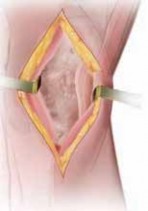

1. A routine diagnostic arthroscopy is performed.

2. The status of the lateral compartment is confirmed.

1. If unexpected lateral compartment osteoarthritis or chondral defects are found, off-loading the knee into that compartment may be detrimental to the longterm results of the surgery (

TECH FIG 1

).

3. The status of the patellofemoral compartment also is confirmed.

1. Significant patellofemoral arthritis (especially of the lateral patellar facet and lateral trochlea) can be ex-

acerbated with an HTO. Such arthritis also can be detrimental to the long-term results of the surgery.

1. Meniscal tears are débrided back to a stable base.

2. Chondroplasty or marrow stimulation is now performed. If the osteotomy is being performed together with a cartilage restorative procedure (eg, autologous chondrocyte implantation), the osteotomy is performed first and then the restorative cartilage procedures are performed, to minimize any trauma to the newly implanted pe-riosteal covering or injected cartilage cells. TECH FIG 1 • A. Arthroscopic image of the medial compartment. Note the bone exposed on the medial femoral condyle and tibia. B. Arthroscopic image following use of a microfracture technique. On entering the lateral compartment, an unexpected cartilage lesion was found on the lateral femoral condyle. Offloading the mechanical axis into the lateral compartment that already is degenerated is a

A B contraindication to the procedure.